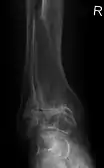

Diagnosis is made with reasonable certainty based on history and clinical examination.[41][42] X-rays may confirm the diagnosis. The typical changes seen on X-ray include: joint space narrowing, subchondral sclerosis (increased bone formation around the joint), subchondral cyst formation, and osteophytes.[43] Plain films may not correlate with the findings on physical examination or with the degree of pain.[44] Usually other imaging techniques are not necessary to clinically diagnose osteoarthritis.

Severe osteoarthritis and osteopenia of the carpal joint and 1st carpometacarpal joint.

Primary osteoarthritis of the left knee. Note the osteophytes, narrowing of the joint space (arrow), and increased subchondral bone density (arrow).